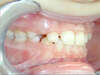

Inversé d'articulé incisif : les incisives du haut et du bas sont à l'envers. Interception en denture mixte.

Correction en denture mixte

Finition en denture définitive